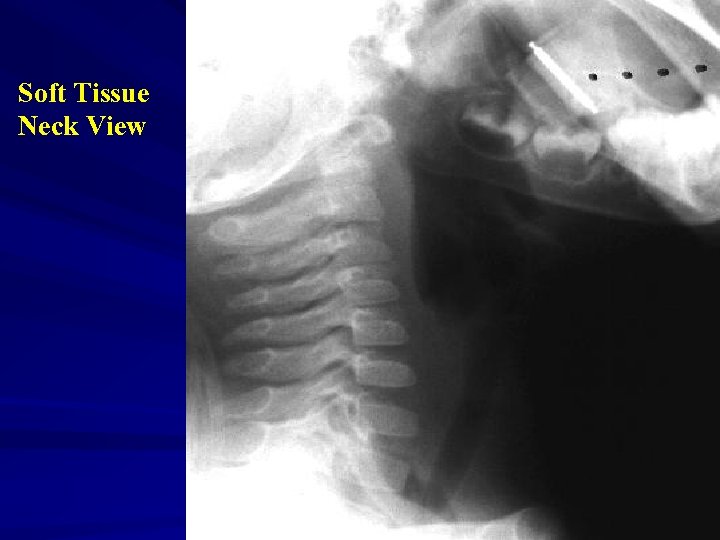

Soft tissue lateral neck radiograph

On Exam … Nasopharynx Oropharynx Bulging forward of the soft palate and nasal obstruction Bulging of posterior phyaryngeal wall or Not visualized Soft Tissue Neck Film Patient position – MILD EXTENSION Positive Film - Retropharyngeal soft tissue > ½ the width of the adjacent vertebral body - may see air in the retropharynx